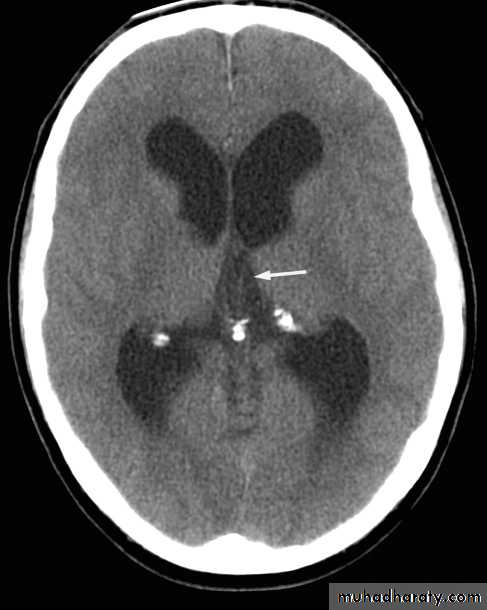

Computed tomography of the brain

• A routine CT examination of the brain involves making 20–30 axial sections.

• The axial plane is the routine projection but computer reconstructions can be made from the axial sections, which then provide images in the coronal or sagittal planes

• The window settings are selected for the brain and are also altered to show the bones

• I.V. contrast indication

• IV contrast tends not to be used in patients who are known to have a very recent cerebral haemorrhage or infarct. Areas of calcification may be obscured on post contrast scans.

The cardinal signs of an abnormality on a CT scan are:

• Abnormal tissue density• Mass effect

• Enlargement of the ventricles.

Abnormal tissue density

• Abnormal tissue may be of higher or lower density than the normal surrounding brain.• High density is seen with recent haemorrhage, calcified lesions, and areas of contrast enhancement

• Low density is usually due to neoplasms or infarcts, or to oedema, which commonly surrounds neoplasms, infarcts, haemorrhages and areas of inflammation.

Mass effect

• The lateral ventricles should be examined to see if they are displaced or compressed.• Shift of midline structures, such as the septum pellucidum , the third ventricle, or the pineal, is a common finding with intracranial masses.